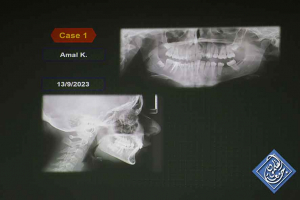

أ.د.عمر حشمة، عميد كلية طب الأسنان في جامعة دمشق ومحاضرته بعنوان” الأكياس الورمية السليمة في الفكين”

د.مازن مراد، اختصاصي في مداواة الأسنان، مشرف على تطبيقات الكومبوزيت في المركز الوطني NDC، ومحاضرته بعنوان ” الدليل العملي في ترميمات الكومبوزيت (حالات سريرية) ”